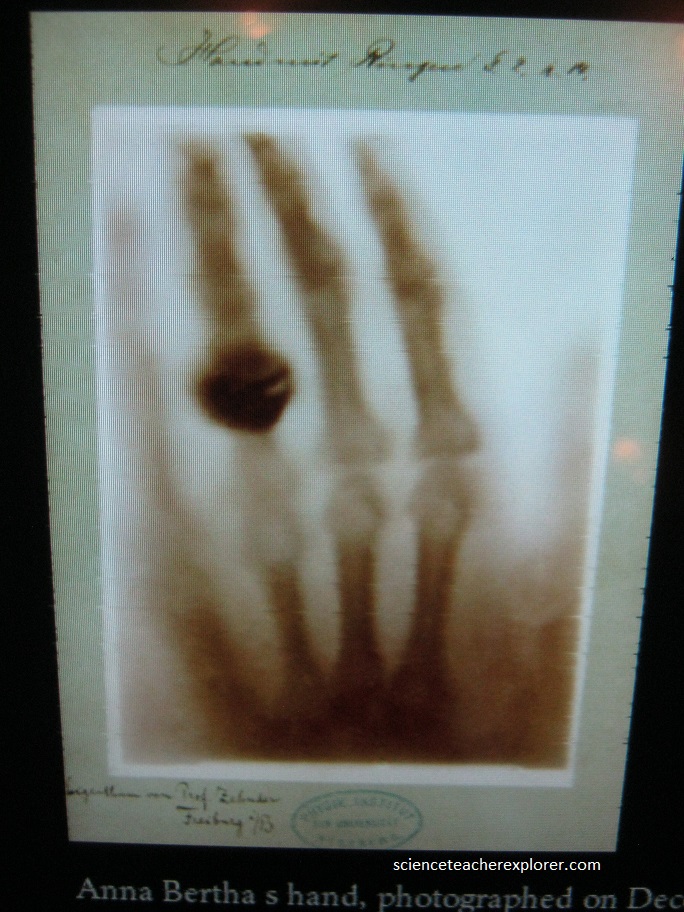

For the Germans, “to x-ray” is “röntgen”. Nowadays everything in the Deutsches Röntgen Museum in Lennep is connected with the invention which made Röntgen famous throughout the world: x-rays. Below is a historical image of the first X-Ray taken of the hand from Rontgen’s future wife.

Now we take the picture. On one side of whatever is being X-rayed, (say a human hand), is the window through which the beam is emitted; on the other side of the hand is the film. As the X-ray photons meet the atoms in the hand, they will either pass through or be absorbed by them. The softer tissues in the human body, (skin, organs and muscles), are made up of relatively small atoms. The X-ray photons pass right through them and leave their mark as the lighter areas on the film, just like light hitting a camera’s film. The atoms in the bones, (primarily calcium), are much larger, and they absorb the X-rays and stop them from reaching the film. Result: The film has captured an image of the bones in the hand.